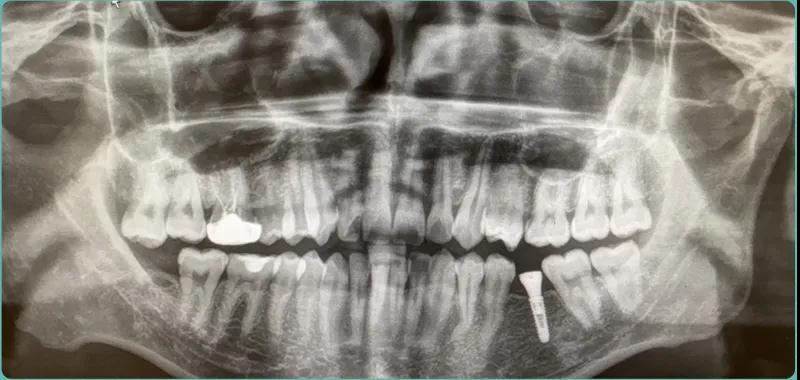

种植嘉宾术前资料介绍,年龄27岁,种植左下颌6号牙。